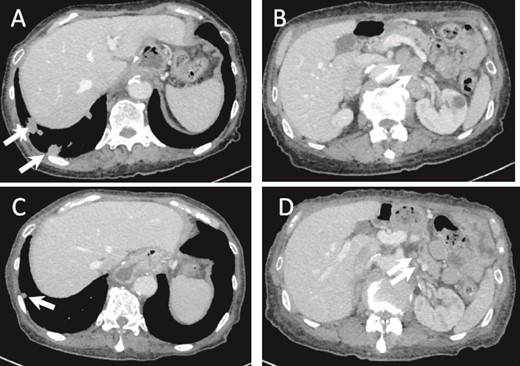

Five months after surgery, a CT scan showed multiple lung and lymph node metastases. CT scan after one cycle of S-1 monotherapy showed partial response (PR) (Fig. 5). Ten months after surgery, the patient became progressive disease (PD). S-1 monotherapy was continued until 1 year and 2 months postoperatively, but treatment was terminated due to deterioration of performance status (PS 3), and the patient died at 1 year and 5 months postoperatively.

(a) CT image 5 months after surgery. Multiple lung metastases are seen (arrows). (B) Intra-abdominal lymph node metastasis is shown (arrows). (C, D) Lung and lymph node metastases after one cycle of chemotherapy show PR (arrows).